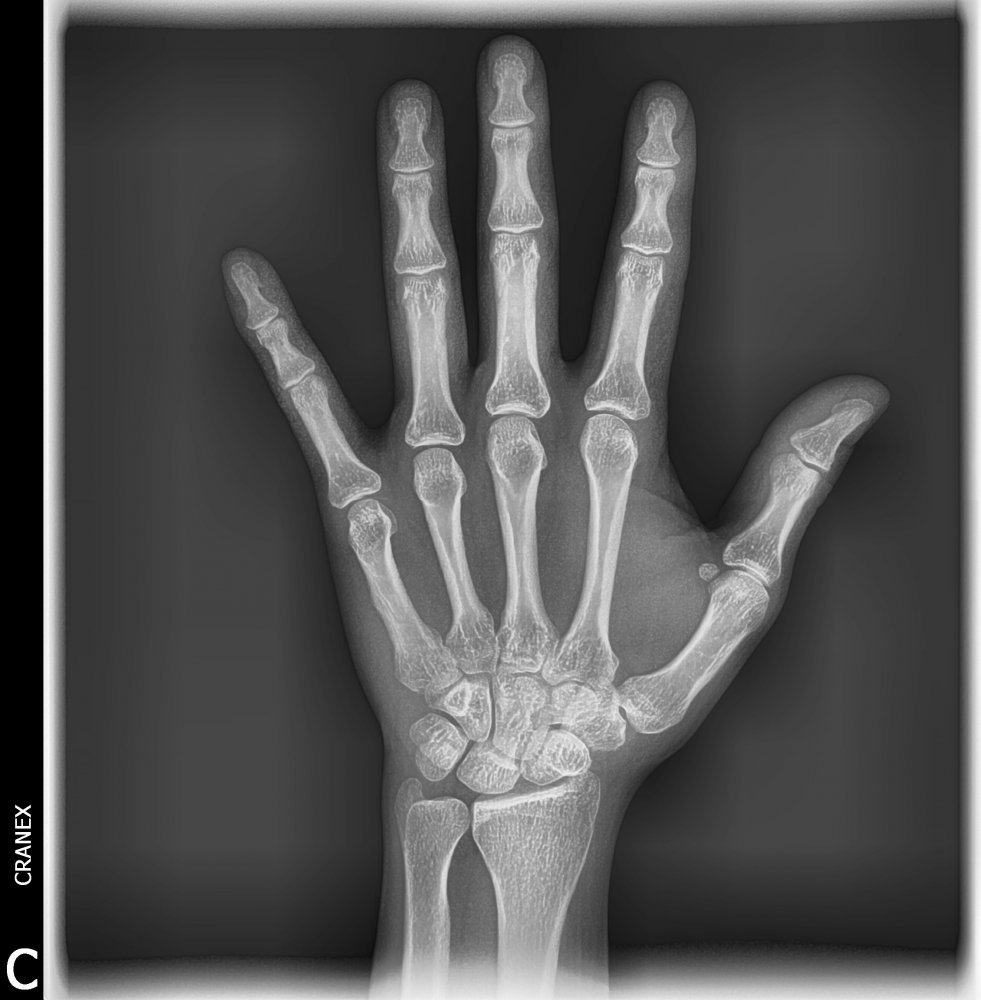

- RX. Carpal (Edad Ósea)